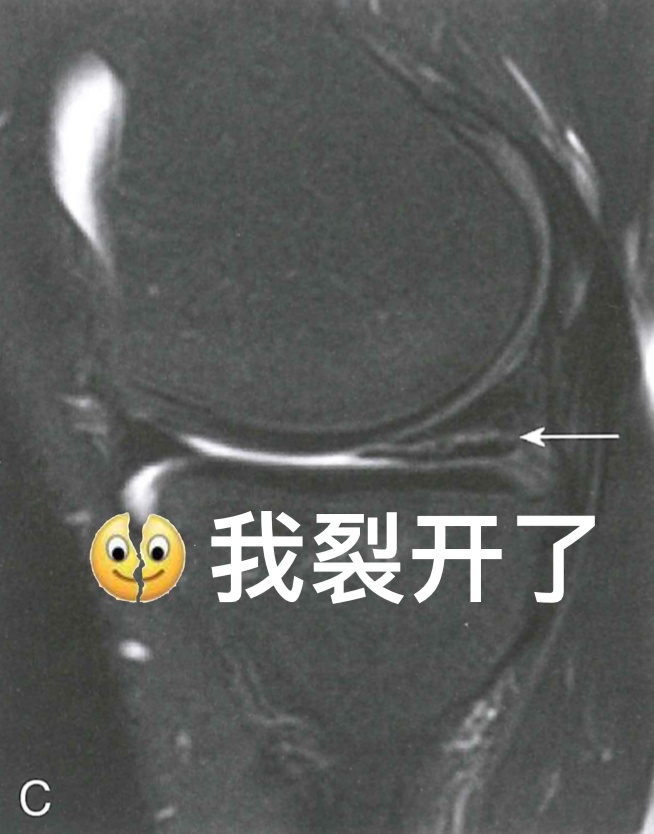

图 7 半月板损伤

除了韧带可能在运动中被扯断、撞坏之外,膝关节里还有两块半月板也很容易受伤。就像坐在硬板凳上屁股硌得难受一样,膝关节上下两个大骨头要是直接硬碰硬,你的膝关节肯定不会好受。而半月板就像两块缓冲垫,能让股骨和胫骨和谐共处,你的膝关节也能正常发挥功能。不过,如果半月板出现了损伤,那你的膝关节可能就不会那么灵活,蹲下站起可能会“咔咔”响,甚至有时好像卡住了一样。这时,MRI也是诊断的重要工具,如果真的存在半月板撕裂,在膝关节MRI上就能看到半月板“裂开”了。